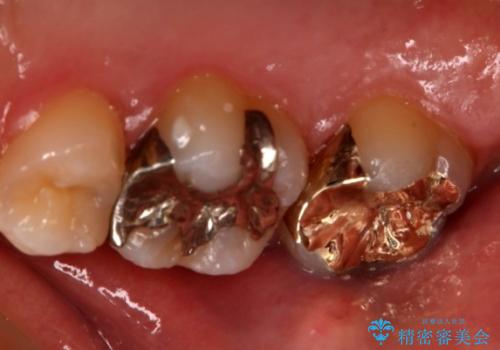

- 右上大臼歯の再治療を希望され来院された患者様です。

切削量と形状を考慮し、インレーでの治療を計画しました。

患者様がゴールドを希望されたのでゴールドインレーを選択しました。